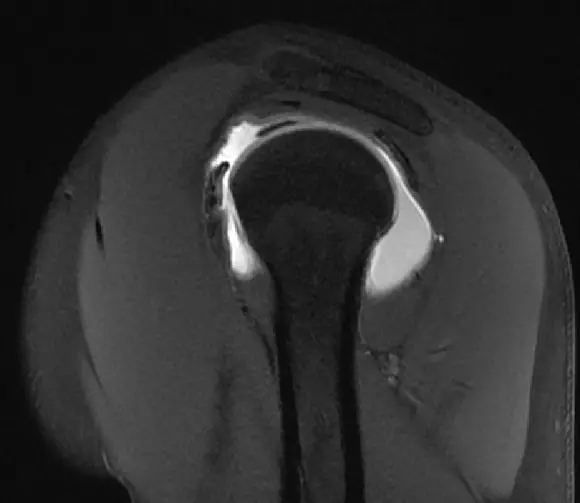

这是一个肩关节造影的磁共振片子,包括肩胛下肌,冈下肌,冈上肌